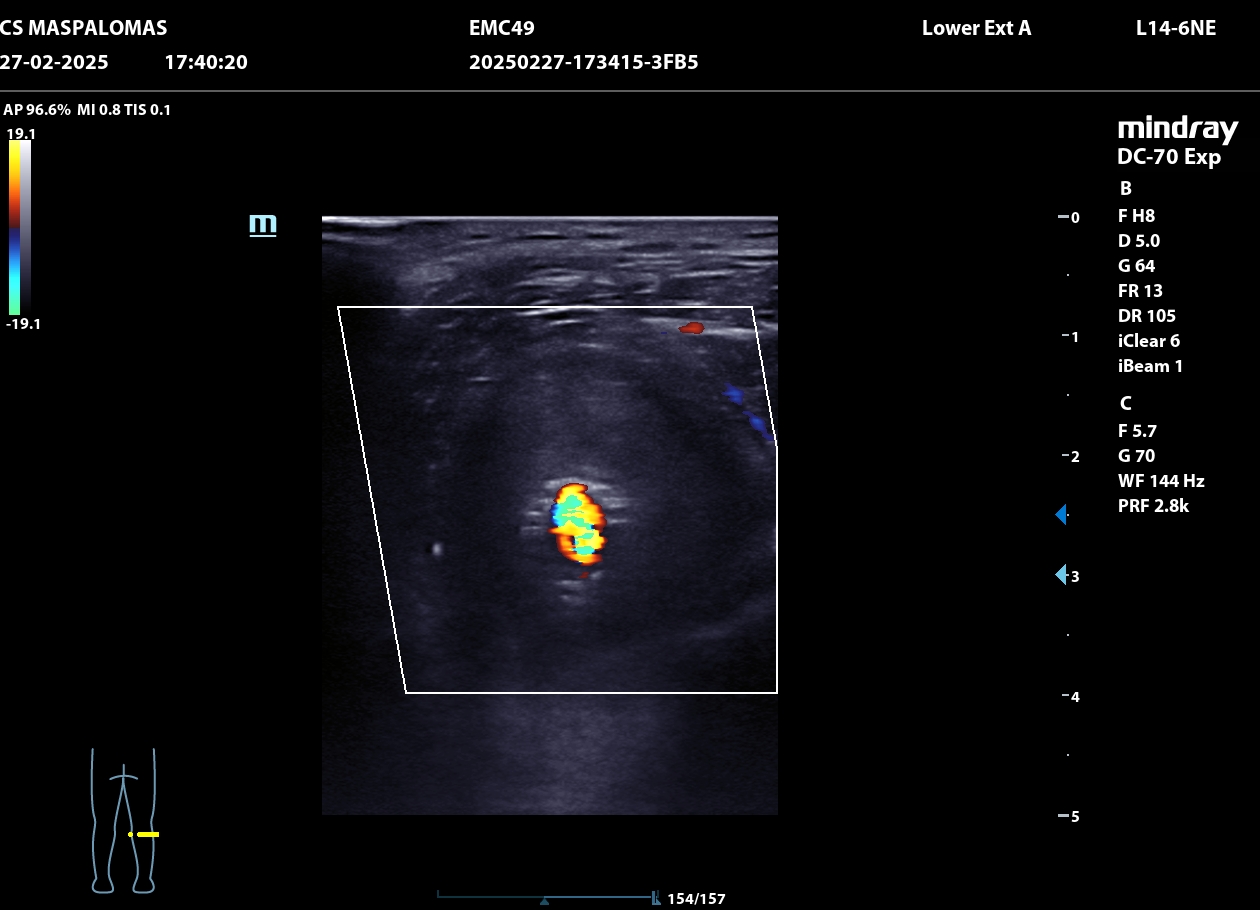

Se realiza ecografía clínica en consulta que revela un aneurisma de la arteria poplítea derecha de 4,66 cm con trombo intraluminal de gran tamaño.

El paciente es derivado a urgencias hospitalarias, se realiza un ECO-Doppler que muestra dilatación de la arteria poplítea derecha de 3 cm con trombo mural, y durante el ingreso en Cirugía Vascular un TAC, confirmando la presencia de un pseudoaneurisma de arteria poplítea derecha de 4,70 x 3,80 cm con trombo mural y salida distal por tres vasos.